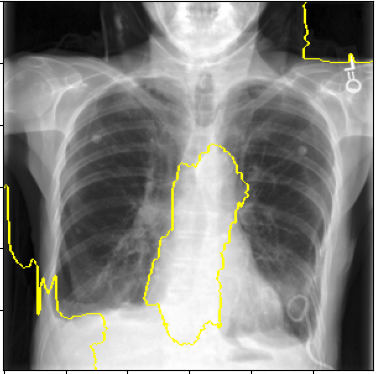

3.3 Interpretability

Post-Hoc Comparisons. We compare our concept-based explanations to post-hoc XAI techniques LIME and SHAP, applied to the baseline InceptionV3 model. The image explanations generated by these techniques disagree with each other and the medical ground truth. We show an example of this observation in Figure 7, where both techniques fail to capture the large mass in the X-ray, and highlight irrelevant regions such as areas outside of the lung as incorrectly important to the classification decision. In contrast, our approach correctly identifies the presence of a mass. More examples are shown in Figure 10.

Refer to caption

(a) Ground Truth

(b) LIME

(c) SHAP

(d) CXR-LLaVA Generated Report

(e) Our Approach

Figure 7: Example of our explanation approach outperforming LIME, SHAP and CXR-LLaVA. Ground truth (a) is a “Large right upper zone mass". LIME (b) and SHAP (c) fail to capture the mass in the X-ray. Most important image regions are bounded by yellow for LIME, and shown in more vibrant green for SHAP. CXR-LLaVA (d) generates a report which wrongly describes the image as non-cancerous. Our approach (e) correctly identifies the presence of a mass.